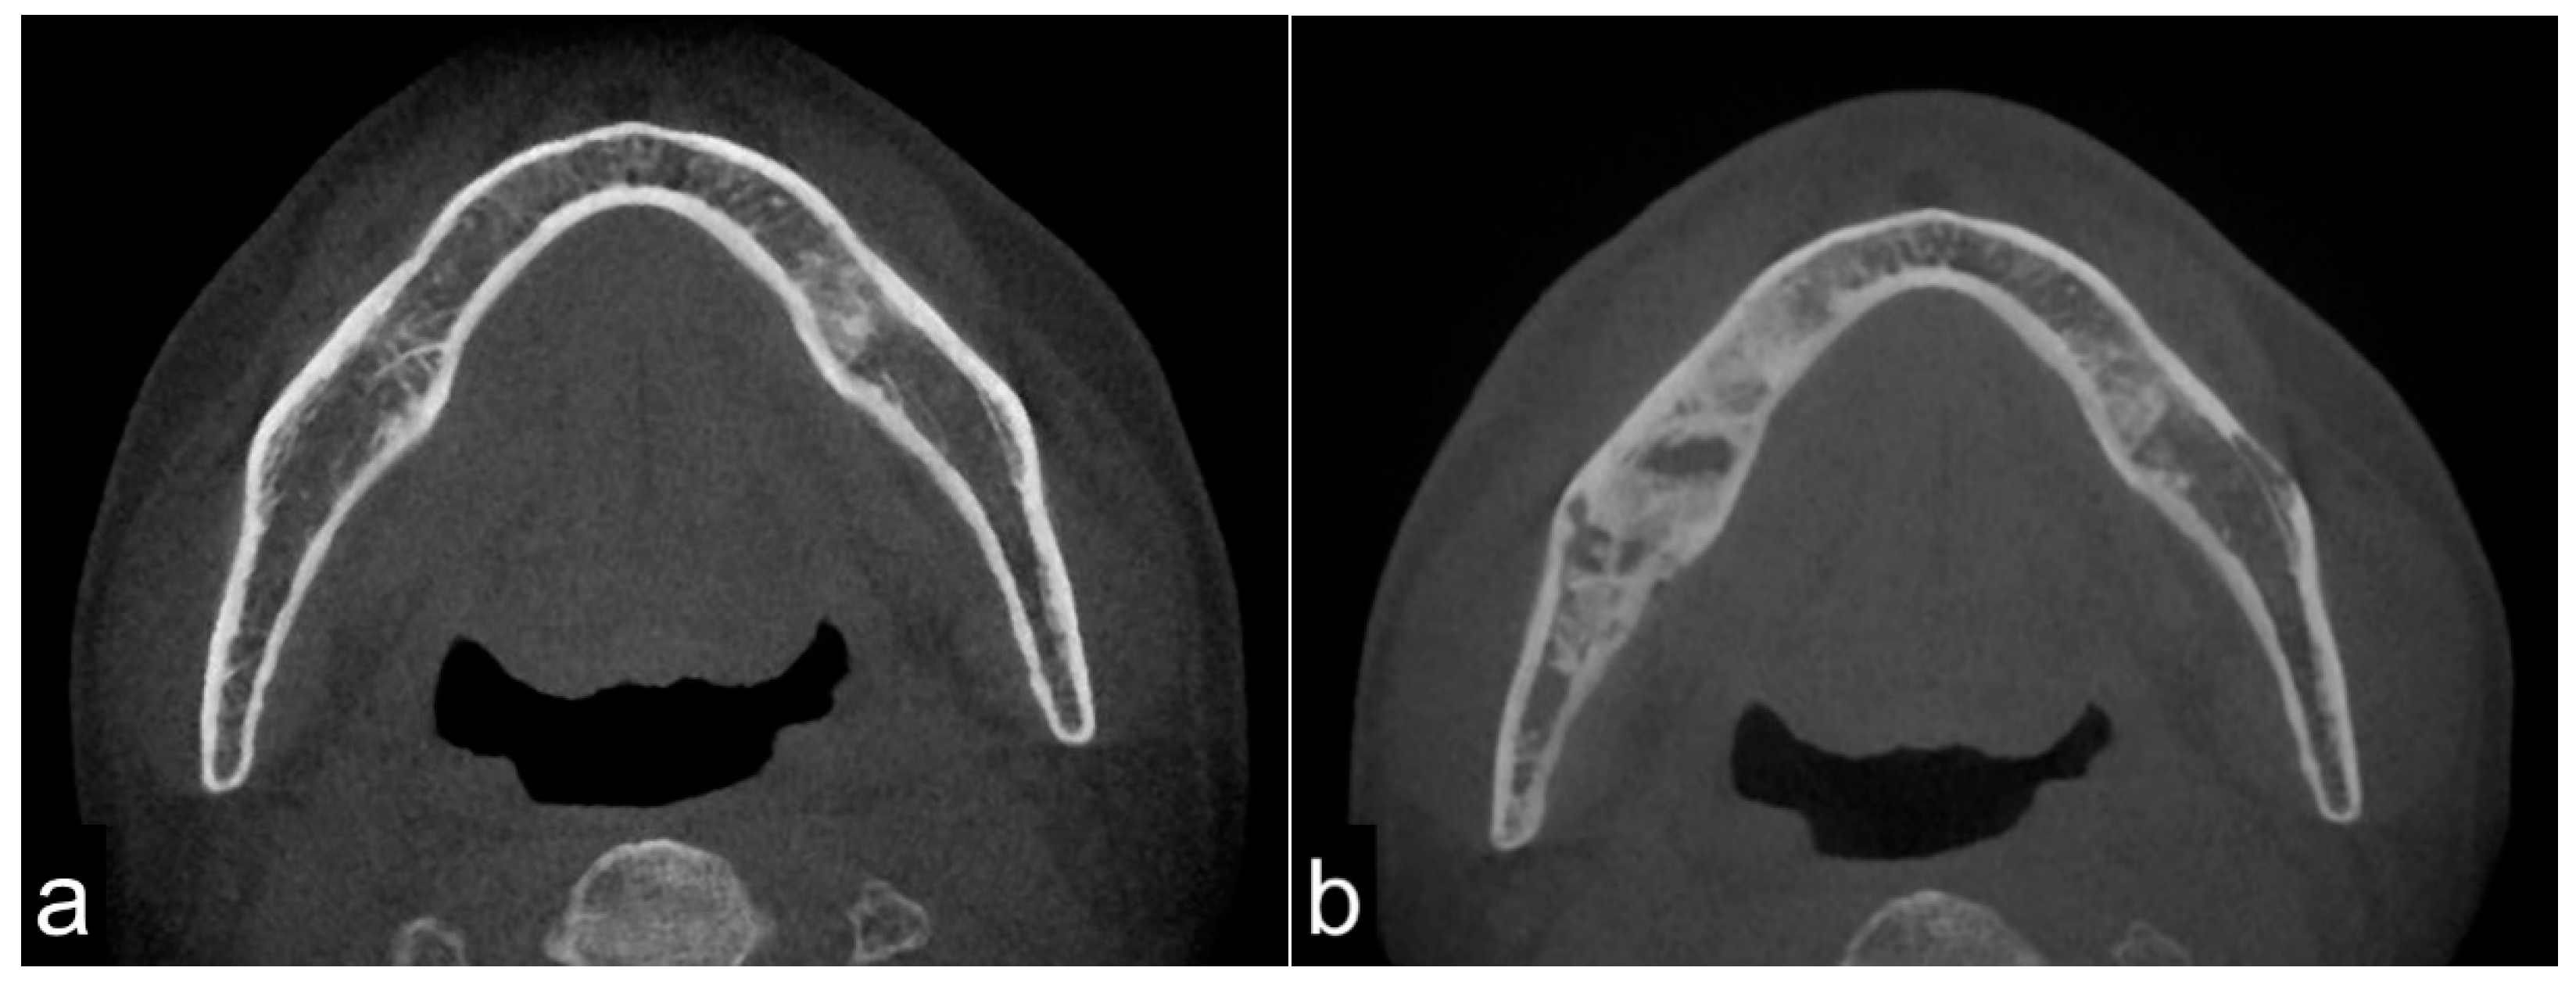

On CT images, homogeneous bone consolidation was observed in 10 (20.8%) patients. Heterogeneous bone consolidation was observed in 30 (62.5%) patients, and six (12.5%) patients showed bone resorption. Using pre-treatment CT data, we compared the levels of bone consolidation. The cancellous bone was sclerosed in 28 (58.3%) sites; however, eight (16.7%) sites did not show clear bone consolidation images, and one (2.1%) site clearly showed bone resorption. Eleven (22.9%) sites did not have sufficient data (Figure 1a,b). Moreover, the periosteal reaction was not observed in 44 (91.7%) sites, and the periosteal reaction was observed in four (8.3%) sites. At first, there were four pathological fracture cases during the observation period, and finally, there were six cases.

Figure 1.

Pre-treatment mandible on axial computed tomography (CT) scan (a) and osteoradionecrosis (ORN) mandible on axial CT scan (b). The image shows bony sclerotic changes with ORN (b) involving the right mandible compared to the pre-treatment mandible in the same lesion without periosteum reaction (arrowhead). These reactions may have been induced by irradiation.